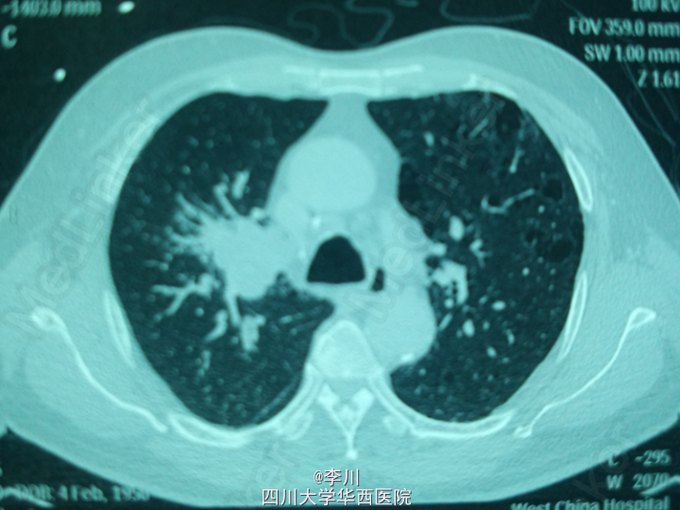

心肺腹查体无特殊异常。行胸部CT示:右主支气管内软组织影,大小约3.6*5.2cm,右上叶支气管开口变窄。纤支镜:右主支气管新生物,完全阻塞右肺上叶支气管;病理:查见鳞癌。

诊断为:右肺中央型鳞癌。于全麻下行右肺上叶切除+支气管袖式成形+系统淋巴结清扫术。术中见:肿块位于右肺上叶,约5cm大小,清扫2,4,7,10,11,12组淋巴结。手术过程顺利。